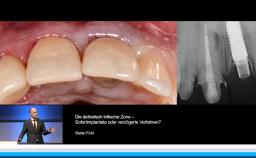

• die Wahl des idealen Implantationszeitpunktes in der ästhetisch kritischen Zone verstehen

Prof. Buser berichtet in dieser Präsentation, die im Rahmen des Deutschen ITI Kongresses in Dresden im Jahr 2015 gehalten wurde. Langzeiterfolg von Implantaten über 20 Jahre, über den optimalen Implantation und Belastungszeitpunkt. Zunächst erläutert er die gewandelte Altersstruktur der Implantatpatienten und definiert die primären und sekundären Behandlungsziele in der Implantologie. Ein zentraler Aspekt der Präsentation stellt die Wahl des idealen Implantationszeitpunktes nach Extraktion mit Focus auf die verzögerte Sofortimplantation in Verbindung mit GBR dar, die auch mit einem informativen OP Video unterlegt ist. Er setzt sich kritisch mit dem Konzept der Sofortimplantologie auseinander und stellt die Ergebnisse der letzten ITI Konsensuskonferenz dar. Er definiert die Belastungszeitpunkte auf der Basis der ITI Konsensuskonferenz. In einem zweiten Schritt wird die Planung der Belastung in den Zusammenhang mit der Verlaufsbeurteilung der Implantatstabilität mittels ISQ Messung gestellt. Am Beispiel des Sinuslift mit primärer Implantation wird abschließend das Konzept eines flexiblen Belastungszeitpunktes auf Basis der ISQ Messung diskutiert.